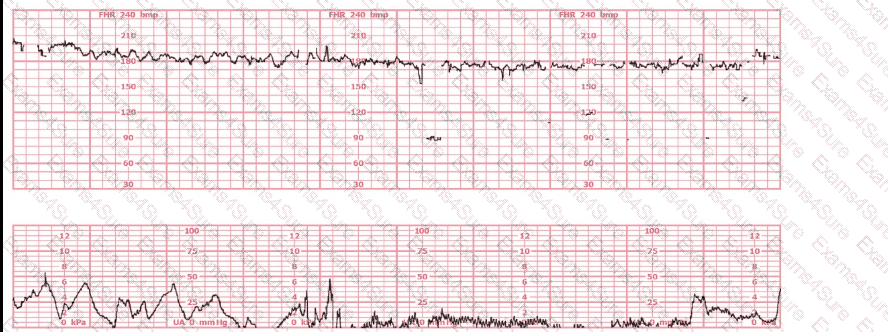

A woman at 41-weeks gestation is being induced. She is 2 cm dilated and is on oxytocin at 8 milliunits/minute. Based on the fetal heart rate tracing shown, the best initial response is to: